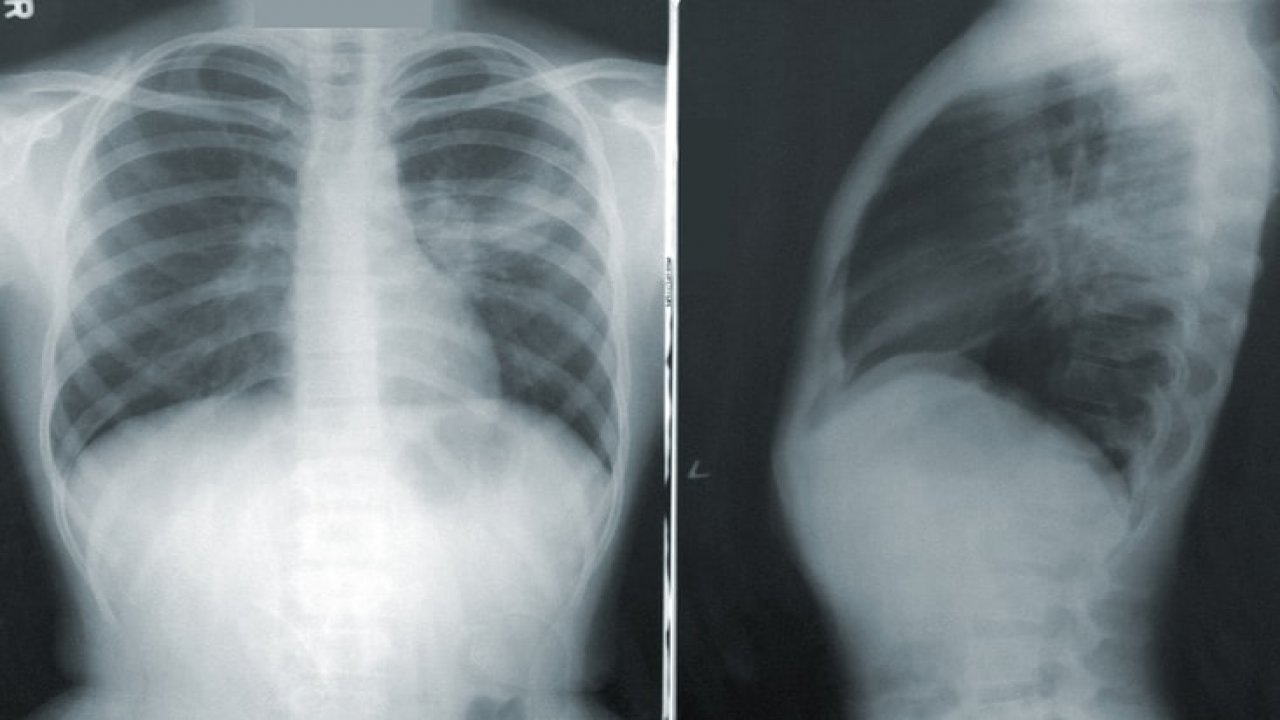

Sağlığınız için akciğerler çok büyük bir öneme sahiptir. Fakat farkında olmadan hayati öneme sahip olan akciğerleriniz su topluyor olabilir. Bunu anlamanız için bazı belirtiler vardır ve bu belirtileri gösteriyorsanız vakit kaybetmeden hemen bir doktora başvurmalısınız.

Sağlığı tehdit eden sorunlardan biri de akciğerin su toplamasıdır. İç Hastalıkları Uzmanı Uzm. Dr. Taner Has, belirtileri ve neden su toplandığını ayrıntılarıyla anlattı. Has'a göre, ateş, nefes darlığı, göğü ağrısı gibi belirtiler akciğerde su toplanmasının habercisi.

Akciğerlerin su toplaması ciddi problemlere yol açmaktadır. Peki akciğerlerde su toplandığını nasıl anlayabiliriz? Bu problemin bazı belirtileri vardır. Sıralarsak şöyle diyebiliriz: